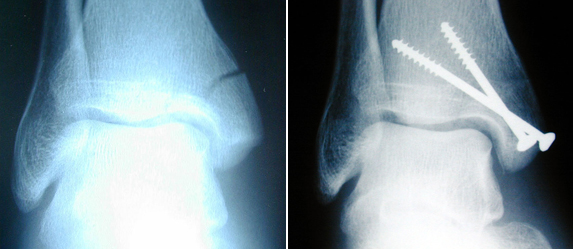

Well I broke my ankle 8 days ago and I am still waiting for surgery. I meet tomorrow with the surgeon to see if the swelling is down enough to do the surgery. I know they will be putting in metal plates and screws on both sides of my ankle. And I am not ready to sit and do nothing. So what I am asking is that anybody who has had this surgery how long before I can at least walk on it or even drive.

I broke my right ankle in 93. I have a plate & twelve screws in it. You can have them removed later but I didn't see the point in it.

I work for an orthopedic surgeon and have worked in ortho for almost 15 years. The ankle joint is complex so much depends on what was fractured (was it the lateral malleolus, calcaneus, distal fibula, distal tibia, talar dome or a combo of these?) as well as the type of fracture. There are also many types of fractures but I'm assuming you probably have a displaced comminuted fracture if you are having surgery. Your downtime also depends on your age, if you smoke and general overall health (diabetes etc) but what I've seen over the years is at least 3 months up to 6 months. An important part of recovery is physical therapy and following the recommendations of orthopedic surgeon as far as activity levels. If you try to do too much too soon you can actually do more damage on top of the traumatic damage to the joint and this will increase your healing time. Remember that your ankle joint supports the majority of the weight of your body. You'll probably be in a cast for a few weeks and then into a Cam walker or walking boot. Not sure if this helps and I wish you a speedy recovery.

As for as my ankle goes I know they will be putting plates and screws on both sides. I think my skin is the only thing keeping my foot attached other the cast they keep putting on.